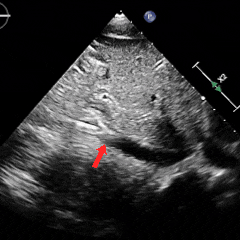

经胸右心声学造影:经左肘静脉注入震荡生理盐水(8mL生理盐水+1mL回抽静脉血+1mL空气经震荡制成),上腔、右房依次显影,造影剂完全充盈右心后,平静呼吸时,左房内即可探及微泡回声,约20-30个/切面/帧;瓦氏呼吸释放即刻,左房内探及微泡回声,不可计数。

术前静息状态经胸右心声学造影(中量)